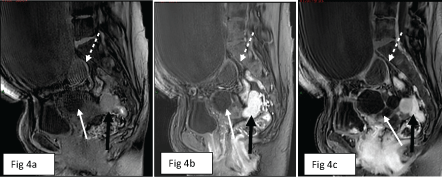

Abdominal US (Figure 1) identified a 23 cm cystic mass in the central abdomen, most probably of right ovarian origin. The lesion contained cystic material with internal echoes; no solid component was identified (Figure 1a). In addition, a multicystic 9 cm mass was demonstrated posterior to the bladder, most probably of left ovarian origin. This second mass had thick septations and various fluid echogenicities (Figure 1b).

Figure 1: Large abdominal cyst with internal echoes at level of mid abdomen (arrow in a) and multicystic left ovarian lesion in the pelvis (arrow in b) on abdominal US examination. View Figure 1